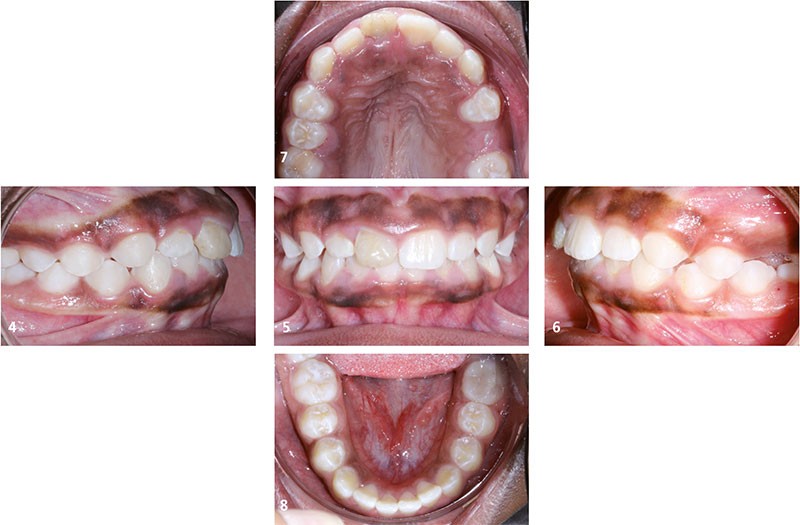

Situation clinique (fig. 1 à 9)

À l’examen clinique, Orlhane présente une classe I biproalvéolie aggravée par 11 fracturée et 25 enclavée et une classe II canine légère gauche. Cette malocclusion est associée à une classe II squelettique par promaxillie sur un schéma facial hyperdivergent. Il est décidé de ne pas traiter la biproalvéolie et la classe II squelettique modérées d’origine ethnique chez cette patiente.